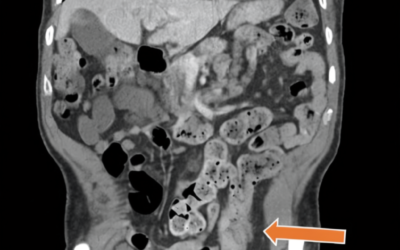

When Crohn’s Disease Masquerades as Another Condition: A Critical Lesson in Accurate Diagnosis

For many of us living with Crohn’s disease, the journey to diagnosis can feel like navigating a medical maze. But what happens when even experienced healthcare…